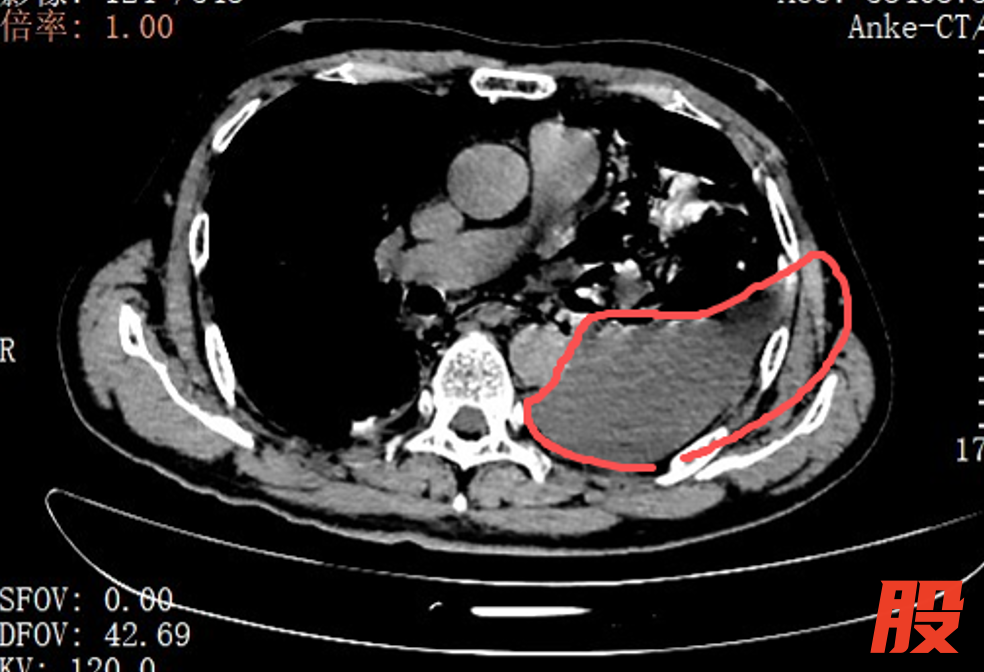

红圈区域是食物残渣、消化液破入食管